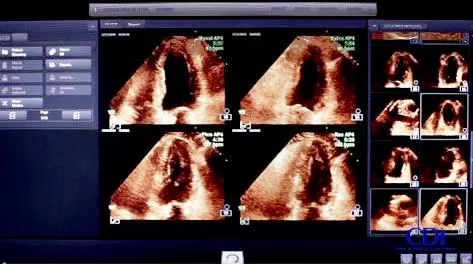

A Ecocardiografia de Stress é um exame cardiológico avançado utilizado para avaliar o desempenho do coração em situações de esforço físico ou simulado por medicamentos. É especialmente importante para investigar a presença de isquemia miocárdica (falta de irrigação sanguínea no músculo cardíaco) e auxiliar no diagnóstico e acompanhamento de doenças coronarianas.

Trata-se de um exame que combina a ecocardiografia (ultrassom do coração) com o aumento da frequência cardíaca induzido por exercício em esteira/bicicleta ou pelo uso de medicamentos, como a dobutamina. O objetivo é observar como o coração reage ao esforço e se o fluxo sanguíneo para o músculo cardíaco é suficiente durante momentos de maior demanda.

Registro das Imagens

- Durante o esforço e logo após, novas imagens do coração são registradas para comparar o funcionamento cardíaco com o repouso.

- O cardiologista analisa se há alterações na contração do músculo cardíaco que indiquem isquemia.